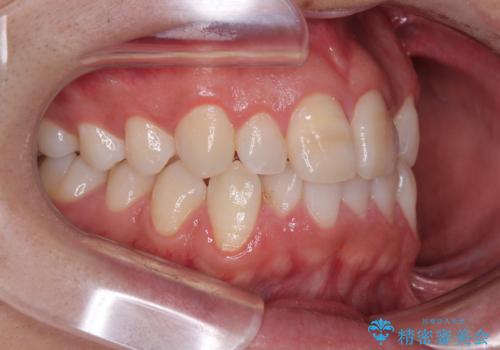

- 「上下の前歯がガタガタしているのが気になる」とのことで来院された患者様です。

上下顎前歯部に叢生(歯の重なり・ガタつき)を認め、見た目だけでなく、歯磨きのしにくさも気にされて来院されました。

そのため今回は、プラスチックブラケット+メタルワイヤーによるクリアブラケットによる治療を選択しました。